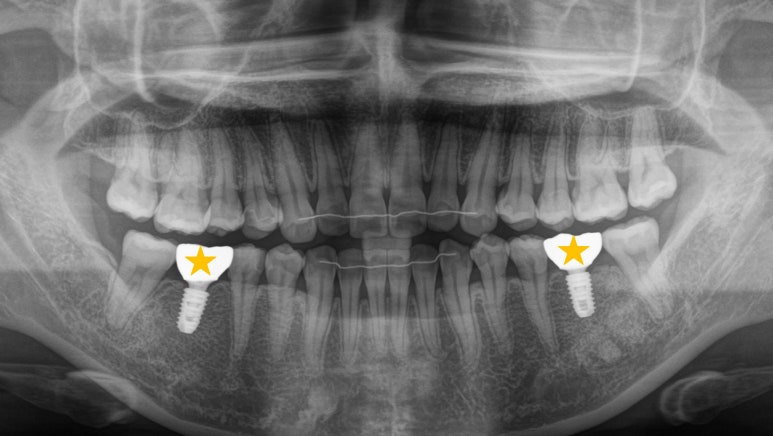

엑스레이를 보면서

한 번 더 정리해 보자면

이 환자가 해결해야 될 문제는

크게 4가지 정도가 있습니다.

삐뚤빼뚤한 앞니 총생

왼쪽 아래 잔존 유치

오른쪽 아래 어금니 기울어짐으로 공간 부족

충치가 생긴 사랑니

인비절라인을 이용하여

어금니에 임플란트를 심을 공간이

확보되었다면

그 자리에 픽스처를 심습니다.

이때도 물론 하치조 신경을 고려하여

안전한 식립을 해드렸습니다.